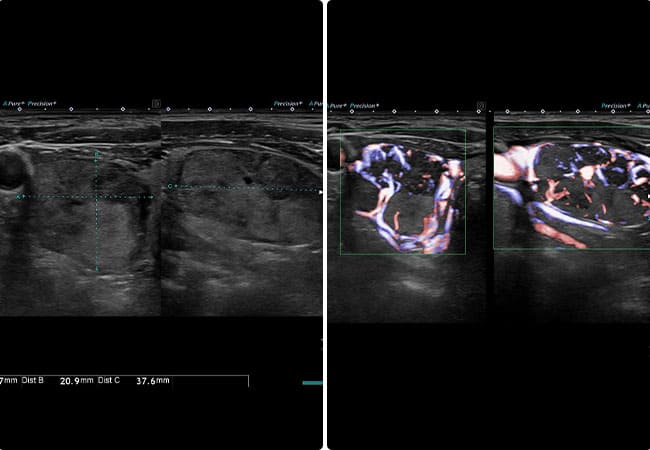

エコー所見では、内部は低エコーで血流は認めません。腫瘤性病変がないか確認していきます。

甲状腺の嚢胞は、液性成分が単純な袋状になったものであることは少なく、結節性病変の変性・壊死や出血などの変化によって液体成分に置換されて起こることが多く、そのため嚢胞壁付近に結節を伴うことが多くあります。結節の性状によっては、後ほど説明する甲状腺乳頭がん(嚢胞形成型)が鑑別となるため、嚢胞でも注意を要する症例があります。

液体が溜まった袋状の構造。触ってみると柔らかく、良性であることがほとんどです。